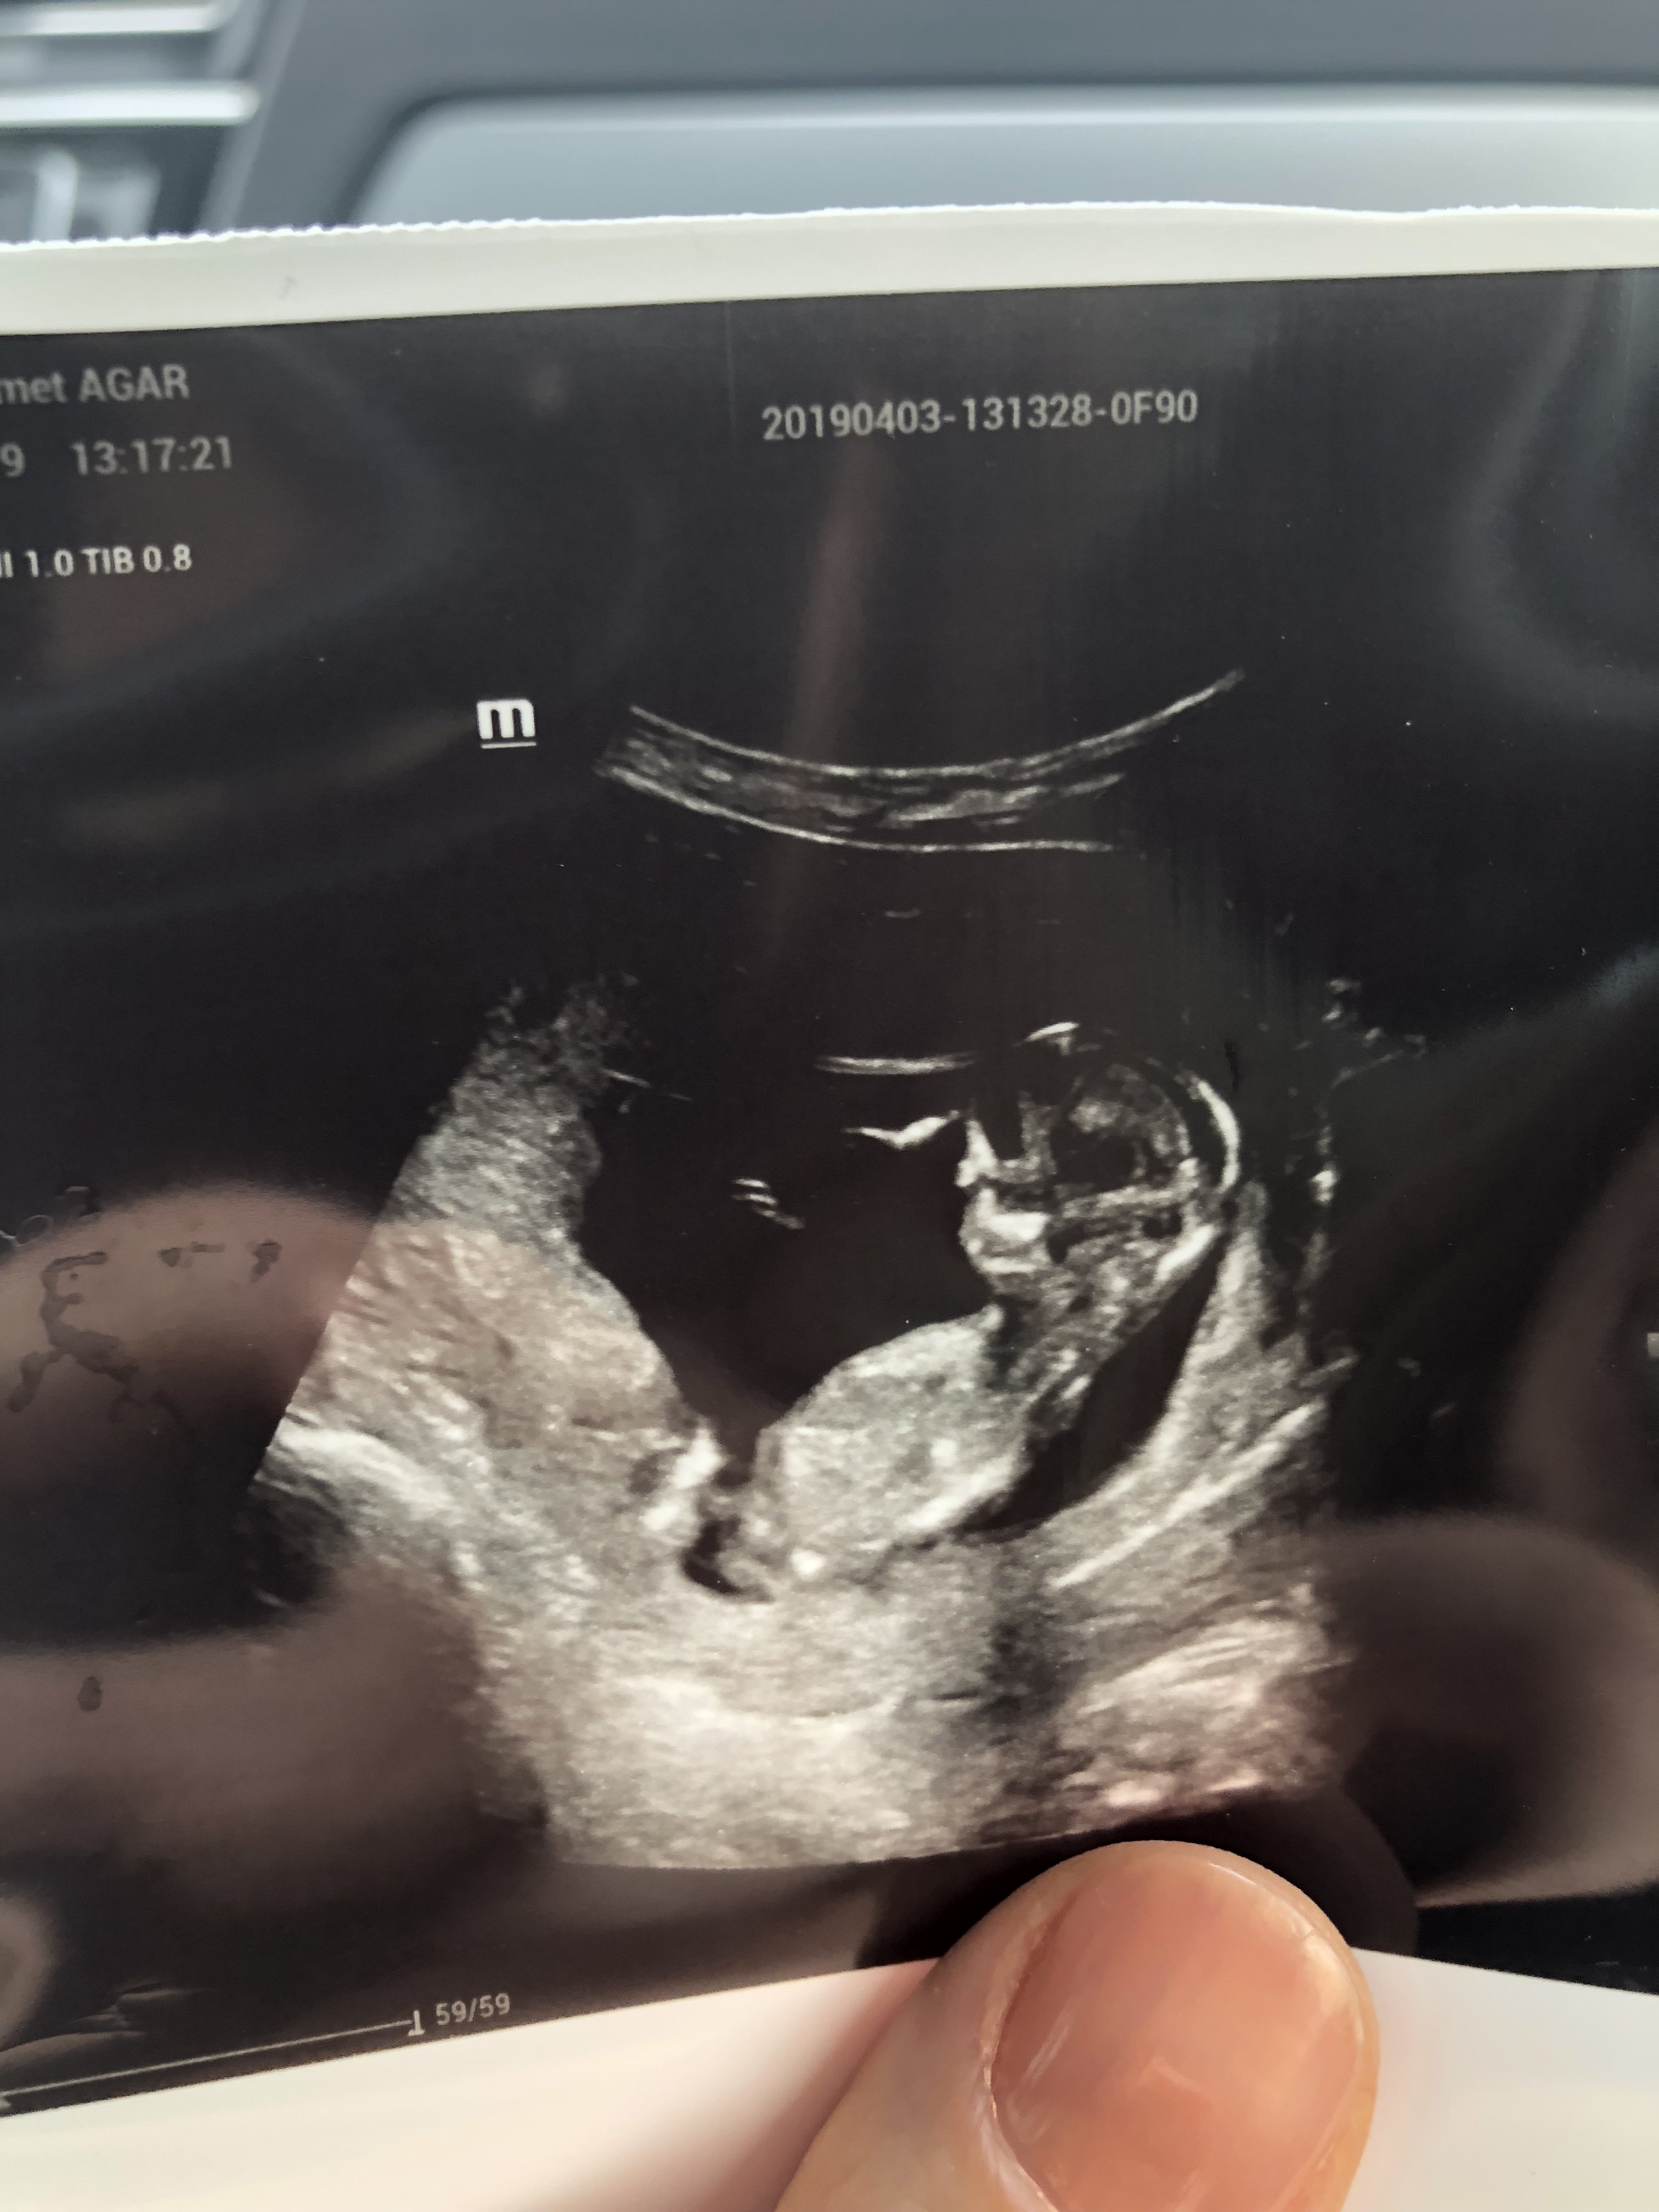

B Boncuk23 Yeni Üye Üye 16 Nisan 2019 #596 Sevimli cadı' Alıntı: Nub çıkıntısı belli olmuyor doktor konumuna göre değerlendirme yapmıştır . Doktor cinsiyetini görebildi mi? Genişletmek için tıkla ... Merhaba rica etsem benim ultrason fotolarıma da bakabilir misiniz teşekkürler Ekli dosyalar 20190411_231719.jpg 859,8 KB · Görüntüleme: 977 20190411_231635.jpg 1.003,5 KB · Görüntüleme: 693 20190411_231645.jpg 1 MB · Görüntüleme: 755 20190411_231635.jpg 1.003,5 KB · Görüntüleme: 768

Sevimli cadı' Alıntı: Nub çıkıntısı belli olmuyor doktor konumuna göre değerlendirme yapmıştır . Doktor cinsiyetini görebildi mi? Genişletmek için tıkla ... Merhaba rica etsem benim ultrason fotolarıma da bakabilir misiniz teşekkürler